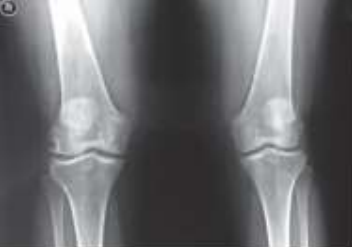

A osteoartrite (OA) é a mais frequente das artrites, sendo causa importante de incapacitação decorrente de dor e/ou destruição articular, com grande custo pessoal e social. Observe as alterações típicas de osteoartrite na imagem a seguir.

Radiografia de joelho com osteoartrite.

Em relação a estas alterações radiológicas, assinale a alternativa incorreta.